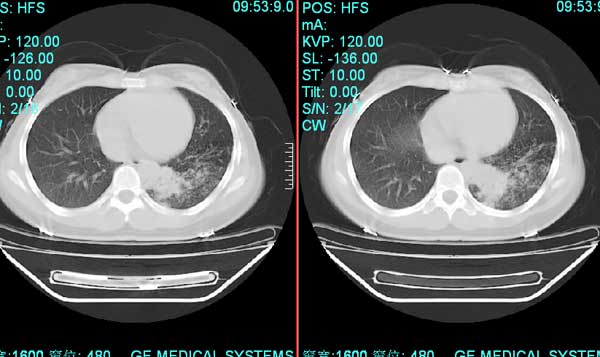

以下是引用pujunzhi在2008-7-1 20:03:00的发言:[br]支持楼主意见!两肺继发性肺结核伴多发空洞形成。